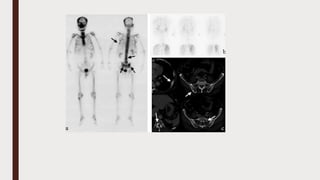

A case of osteolytic-type bone metastasis (patient #2). Eighty-year-old male

patient with a chest wall tumor. BS showed heterogeneous uptake in bilateral

ribs (a). BS diagnosis without clinical information could not detect osteolytic

lesion in the left upper rib, whereas BS diagnosis with clinical information was

able to detect the osteolysis. Chest X-ray revealed chest wall tumor, but no

osteolytic lesion (b). FDG-PET showed high accumulation of FDG in the left upper

chest wall (c). MRI: Gd enhanced 3D-VIBE (fat-suppressed 3D gradient-echo

technique with a volumetric interpolated breath- hold examination). Gd enhanced

MRI showed poorly enhanced left rib tumor surrounded by well enhanced

capsule (d). Further evaluation including biopsy and immunohistochemical

analysis sug- gested that a primary bone tumor was negative and metastasis

from a poorly differentiated lung cancer was highly suspected. This patient was

treated by localized radiotherapy against the chest wall tumor; however, he died

of multiple mediastinal lymph node, bone and liver metastases. According to the

clinical course, the final diagnosis of this patient was established as lung cancer

Osteoblastic